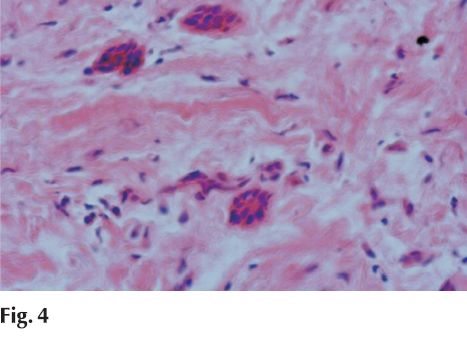

En la pieza de resección quirúrgica bajo la mucosa pavimentosa crece una proliferación fibromatosa fusocelular sin atipías que asocia frecuentes islotes de epitelio odontogénico inactivo sin calcificaciones, que orienta a un fibroma odontogénico periférico (fig. 4).